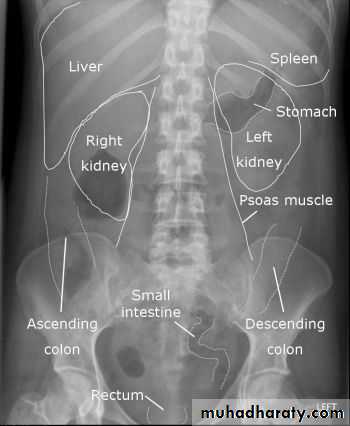

How to look at a plain abdominal film :

• Analyze the intestinal gas pattern and identify any dilated portion of the gastrointestinal tract

• Look for gas outside the lumen of the bowel

• Look for ascites and soft tissue masses in the abdomen and pelvis

• If there are any calcifications, try to locate exactly where they lie

• Assess the size of the liver and spleen